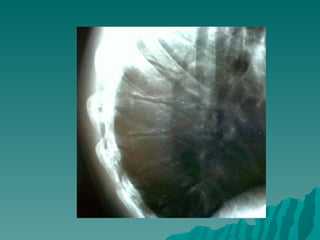

Manyetik Rezonans Görüntüleme

 MR  osteonekrozu erken devresinde

görüntüleyerek tanıyı kolaylaştırır ve

artiküler kıkırdağın sınırlarını net bir

şekilde gösterir.

 Infarktı göstermede çok sensitiftir,

ama iyileşme devrelerini doğru

sınırlar ile ayırmada henüz yeterli

değildir.

 Hastalığın tedavi takibindeki yeri

henüz netleşmemiştir.

Manyetik Rezonans Görüntüleme MR osteonekrozu erken devresinde görüntüleyerek tanıyı kolaylaştırır ve artiküler kıkırdağın sınırlarını net bir şekilde gösterir.  Infarktı göstermede çok sensitiftir, ama iyileşme devrelerini doğru sınırlar ile ayırmada henüz yeterli değildir.  Hastalığın tedavi takibindeki yeri henüz netleşmemiştir.